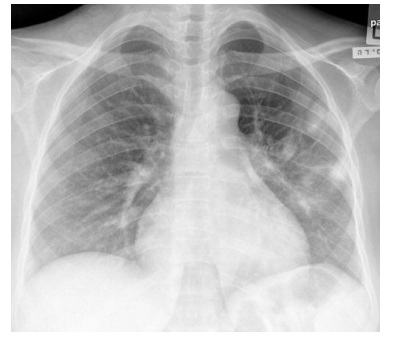

Escolar de 7 anos, acompanhado no ambulatório, foi levado à emergência por dispneia. Mãe relatou que filho estava há 2 dias com mialgia, febre e coriza, evoluindo nas últimas 12 horas com piora da febre e dispneia progressiva. Ao exame, estava febril (39ºC), taquidispneico, PA no percentil 90 e com SpO2 = 88% em ar ambiente. Realizada radiografia de tórax (abaixo). O resultado de RT-PCR foi positivo para influenza A e negativo para Covid-19. Os exames laboratoriais mostraram leucocitose com linfopenia, PCR elevada, e pró-calcitonina baixa.

Enunciado 4059106-1

Diante do caso, qual a principal suspeita diagnóstica e a conduta adequada?